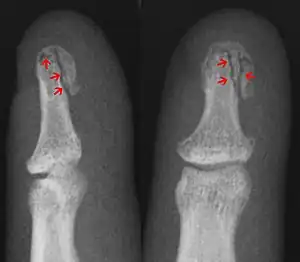

![]() In the fingertip. More images |

Linear fracture | Parallel to the bone's long axis | ||